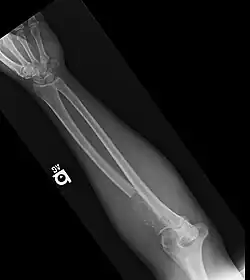

- Bone lesions: one or more osteolytic lesions on skeletal radiography, CT, or PET/CT. * (If bone marrow has less than 10% clonal cells, more than one bone lesion is required to distinguish from solitary plasmacytoma with minimal marrow involvement.)

| Radiology | Normal bone X-rays or solitary bone lesion | advanced lytic bone lesions ("extensive skeletal destruction and major fractures") | |